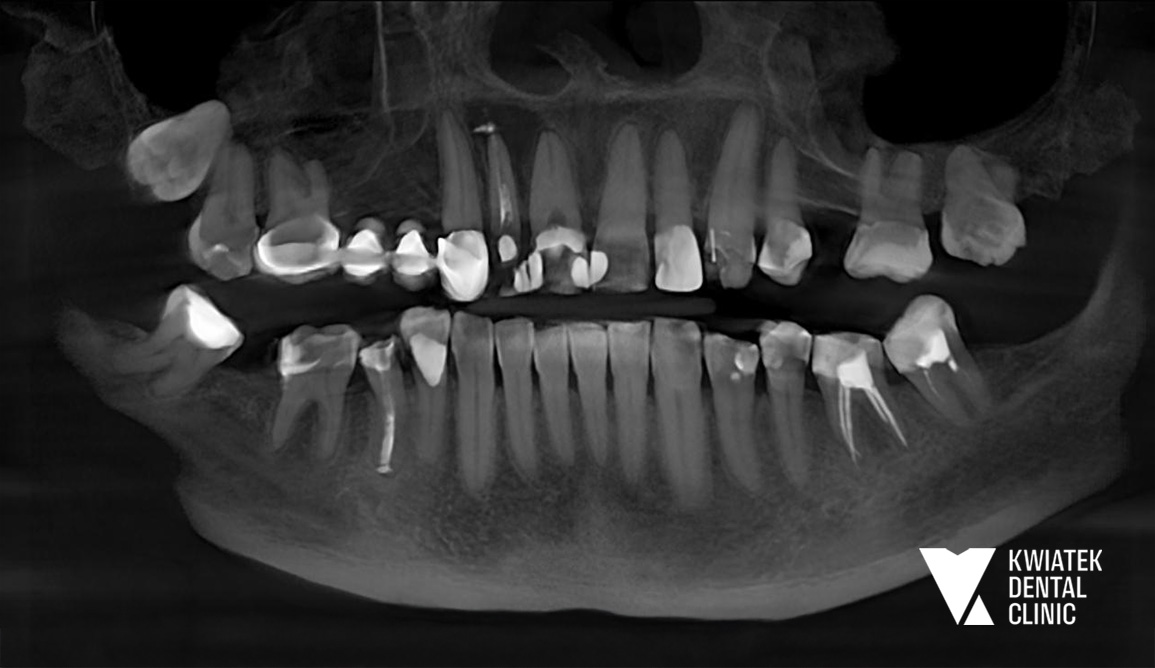

PRZED

Pacjentka zgłosiła się do naszej kliniki z powodu silnych dolegliwości bólowych w obrębie przedniego odcinka szczęki. Leczenie kanałowe jednego z zębów było wcześniej rozpoczęte w innym gabinecie, jednak pomimo kilku wizyt dolegliwości nie ustępowały. W trakcie konsultacji klinicznej stwierdzono bolesność zębów, ich zwiększoną ruchomość oraz objawy wskazujące na proces zapalny w tkankach okołowierzchołkowych. Ze względu na złożoność problemu podjęto decyzję o przeprowadzeniu pełnej diagnostyki oraz zaplanowaniu kompleksowego leczenia.

W celu dokładnej oceny stanu tkanek wykonano badanie tomografii komputerowej CBCT. Badanie wykazało obecność zmiany zapalnej w kości podniebienia w okolicy zębów przednich, o wymiarach około 13 × 10 mm, co wskazywało na torbiel zębopochodną wymagającą leczenia chirurgicznego.

Podczas badania stomatologicznego stwierdzono również szereg dodatkowych problemów:

• nieszczelny most protetyczny w odcinku bocznym szczęki

• zaburzoną płaszczyznę zwarcia

• rotacje zębów oraz ich nieprawidłowe nachylenie

• znaczne starcie powierzchni zębów

• liczne ubytki próchnicowe i nieszczelne wypełnienia

Dodatkowym wyzwaniem terapeutycznym były choroby ogólne Pacjentki, w tym niewyrównana cukrzyca, co wymagało szczególnie starannego planowania leczenia oraz ścisłej kontroli procesu gojenia.